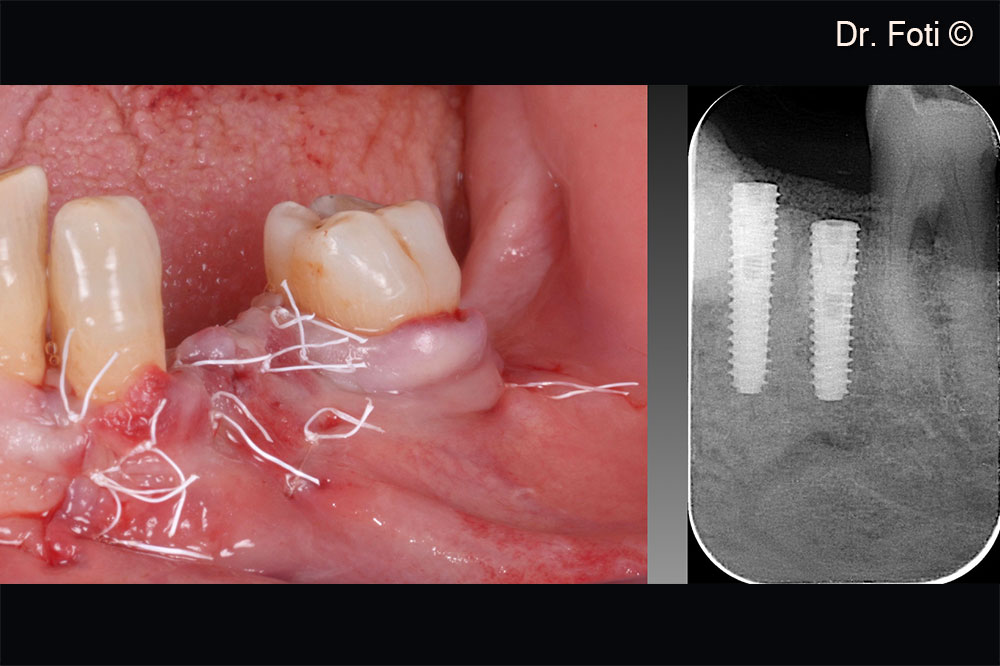

Suture without tension on the edges. Post-operative x-ray.